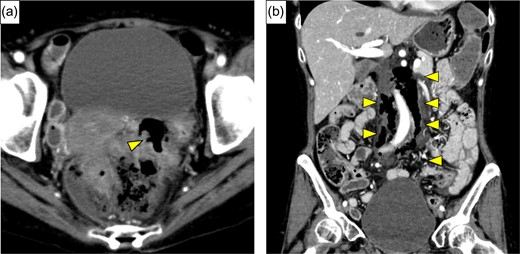

A 54-year-old woman was referred to our hospital because of abdominal pain. She had a history of adult Still’s disease at age 49 and underwent treatment with oral prednisolone, 90 mg/day and cyclosporine, 175 mg/day. A physical examination revealed deep tenderness in the abdomen. Laboratory data showed slight leukocytosis (white blood cell count 9100/μL) with a moderately elevated C-reactive protein level (9.3 mg/dL), while other data, including blood coagulation factor, were within normal ranges. Computed tomography (CT) revealed a small amount of extra-intestinal free air around the rectum and massive retroperitoneal emphysema between the rectum and the left kidney (Fig. 1a and b). Arterial aneurysm was not confirmed. Based on a preoperative diagnosis of rectal perforation, emergency laparotomy was performed, which confirmed peritoneal fluid collection (Fig. 2) and rectum perforation on the retroperitoneal side. After aspiration of the pus and irrigation of the area with saline, Hartmann’s operation was performed (Fig. 3a). Although she was undergoing immunosuppressive treatment, pathological study disclosed no association between diverticulum perforation and cytomegalovirus enteritis (Fig. 3b). On postoperative Day 4, she suffered a sudden intolerable left flank pain; her hemoglobin level was 7.5 g/dL, and slight prolongation of prothrombin time was recognized. CT revealed a left retroperitoneal hematoma and extravasation from the left first lumbar arteries (Fig. 4a). Emergency transarterial angiography and lumbar artery embolization was performed (Fig. 4b). On Day 20 after the first operation the patient felt a sudden right flank pain, and CT confirmed intra-abdominal free air (Fig. 5a). A second emergency laparotomy was performed, which revealed cecal perforation with no obvious masses (Fig. 5b). Perforation resulting from diverticulum was suspected, and an ileostomy without intraperitoneal anastomosis was performed because of concern about anastomotic leakage. Postoperatively the patient developed an intra-abdominal abscess, surgical site infection (Clavien-Dindo IIIa) and pneumonia (Clavien-Dindo II), which were treated conservatively. Although it took time to rehabilitate the patient and control the adult Still’s disease, she was discharged on Day 212 after the first operation. The patient is now doing well with comfortable activity of daily life.

(a) Enhanced abdominal CT showed free air around the rectum (yellow arrow), and strongly suggested perforation of the rectum. (b) Massive continuous pneumoretroperitoneum from rectum was revealed (yellow arrows).